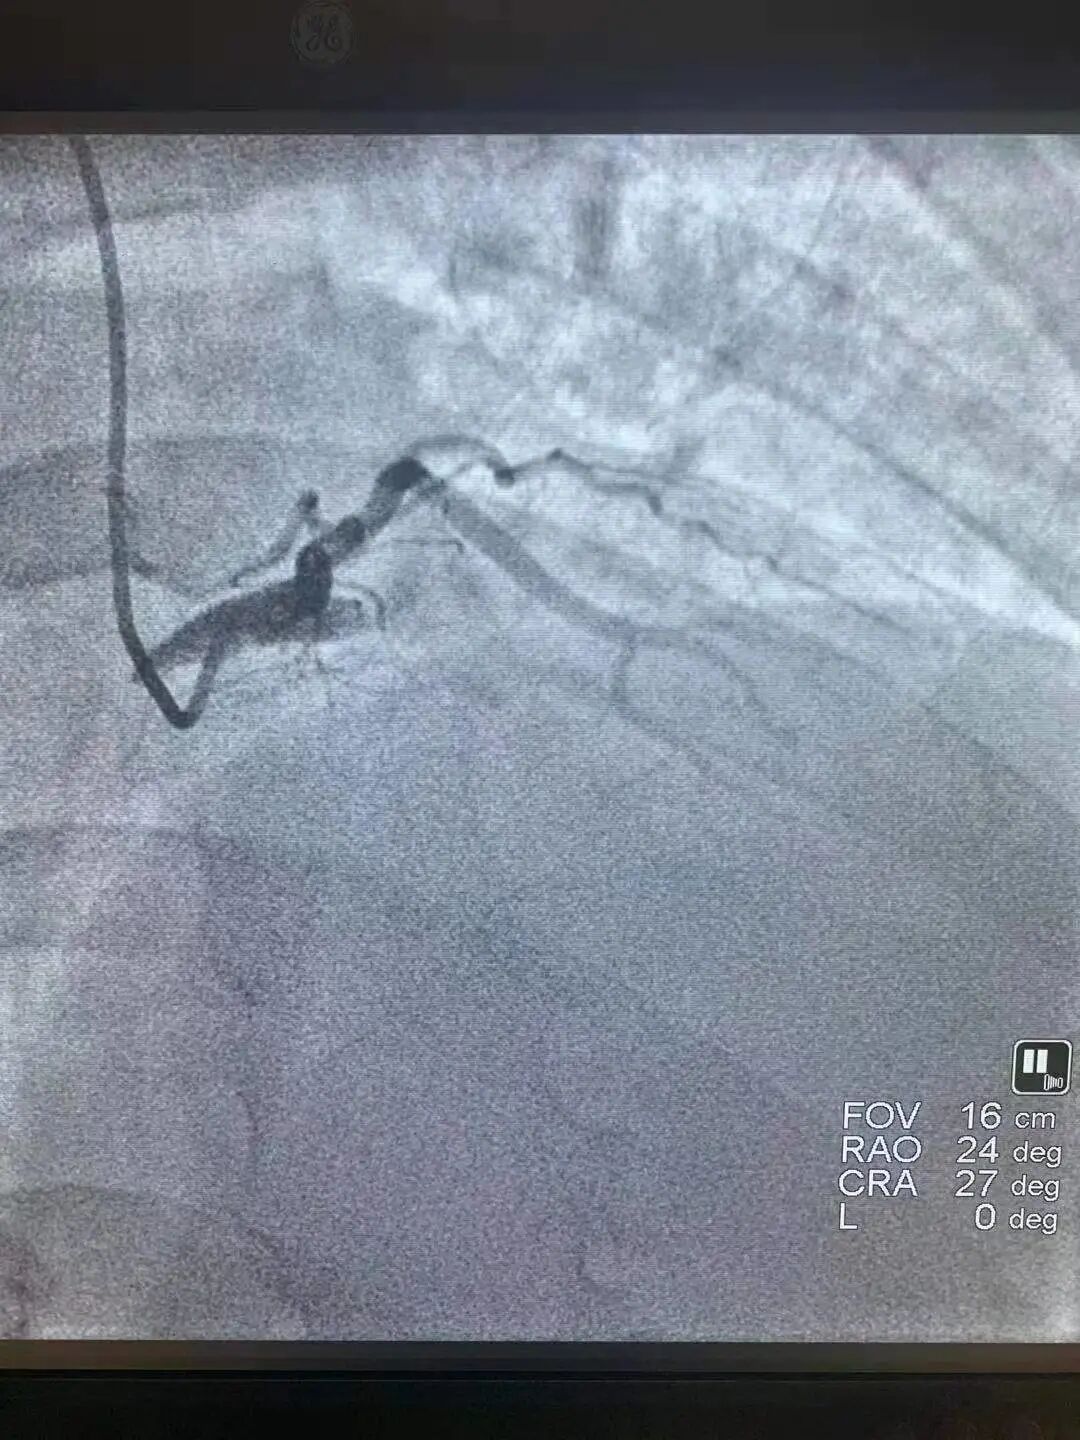

当日19时许,急救中心值班医师曲伟接诊后,通过为患者做心电图,初步判断为广泛前壁心肌梗死。随后通过造影发现患者右冠已经处于慢性完全闭塞状态,而且其前降支近段急性闭塞(心脏三支血管中最重要的一支),回旋支还有80%狭窄(此时患者心肌供血量不足正常情况的1/4),患者病情极其凶险,可谓生命垂危,命悬一线。值班医护人员立即启动绿色通道,刻不容缓地立即将患者送进手术室。

患者进入手术室,病情再次出现变化,血压降至70/40mmHg,脉搏氧饱和度73%,口唇紫绀,生命垂危,ICU、麻醉科、手术室医护人员组成一个与死神博弈的强大阵容,奋力抢救,密切配合。手术中,主刀的医生徐海佳和曲伟发现患者血栓负荷重,遂立马给予血栓抽吸,在多次抽吸出红色血栓后,又马不停蹄地为患者植入心脏支架,由此经过与死神长达1小时赛跑“抢人”,手术得以顺利完成。